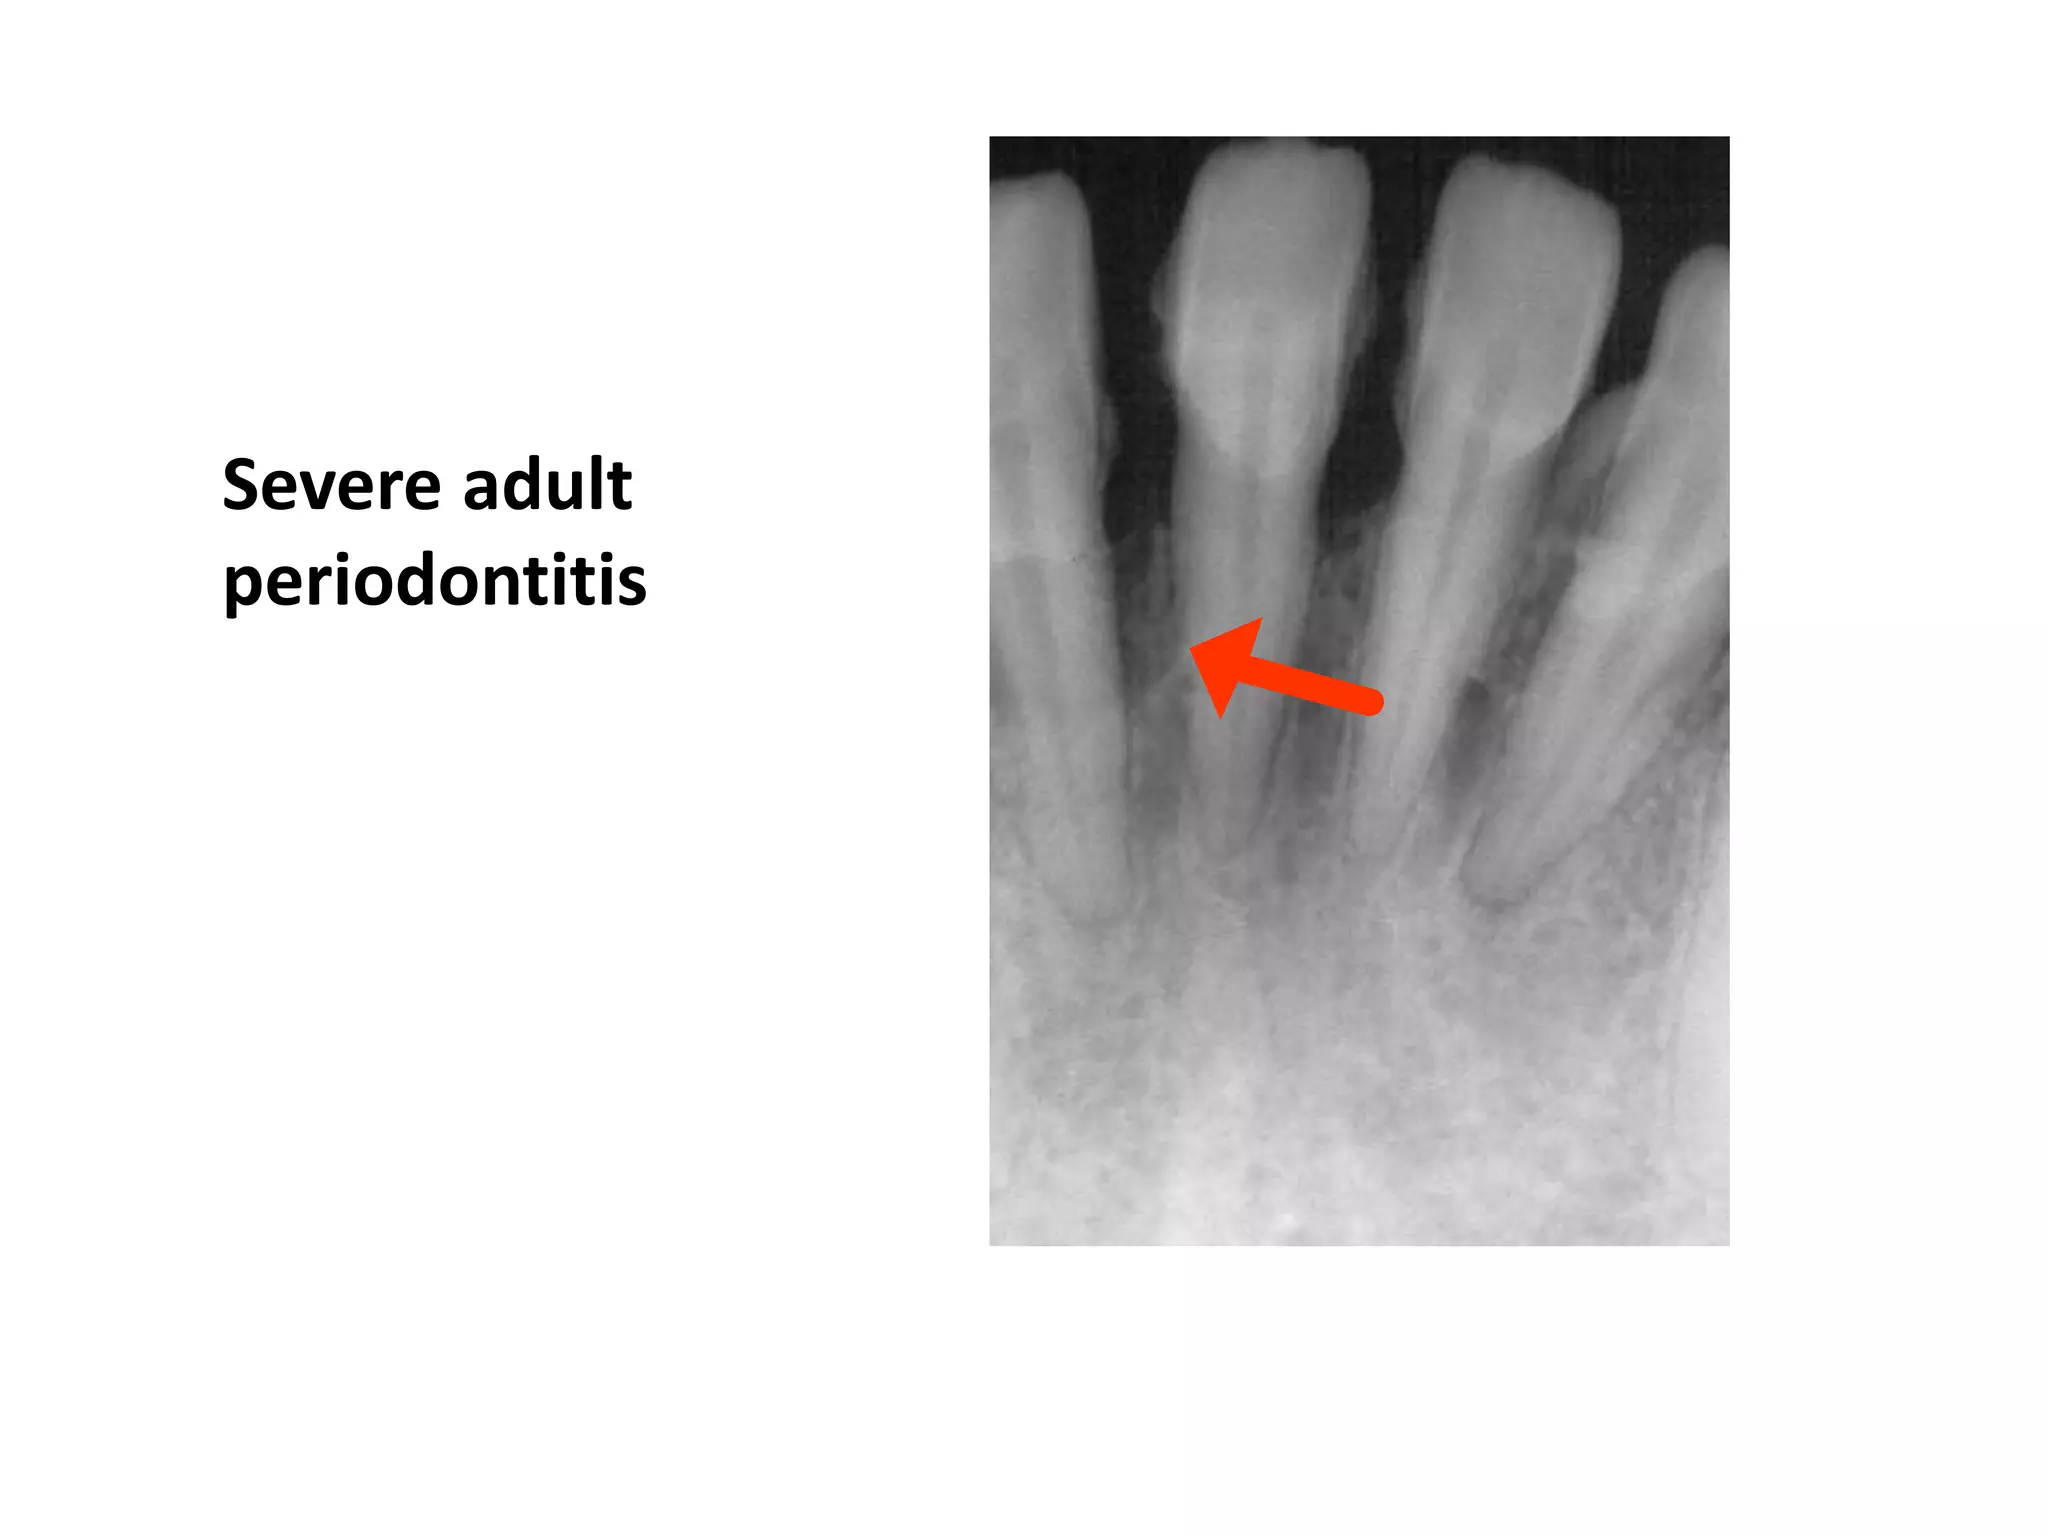

Severe Adult Periodontitis

Tooth mobility

Extensive horizontal bone

loss or vertical osseous

defects

Furcation involvement

Severe adult

periodontitis